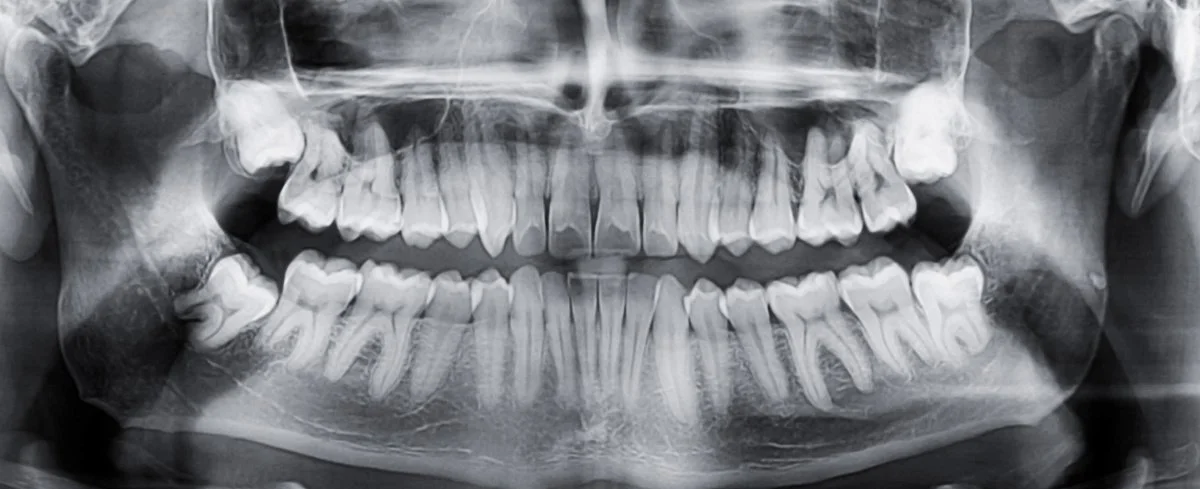

Radiografia panoramică (OPG) – oferă o imagine de ansamblu asupra întregii cavități orale, ideală pentru consultația inițială.

Radiografia retroalveolară (periapicală) – surprinde 1–2 dinți și zonele din jur, utilă pentru evaluarea detaliată a unei probleme punctuale.